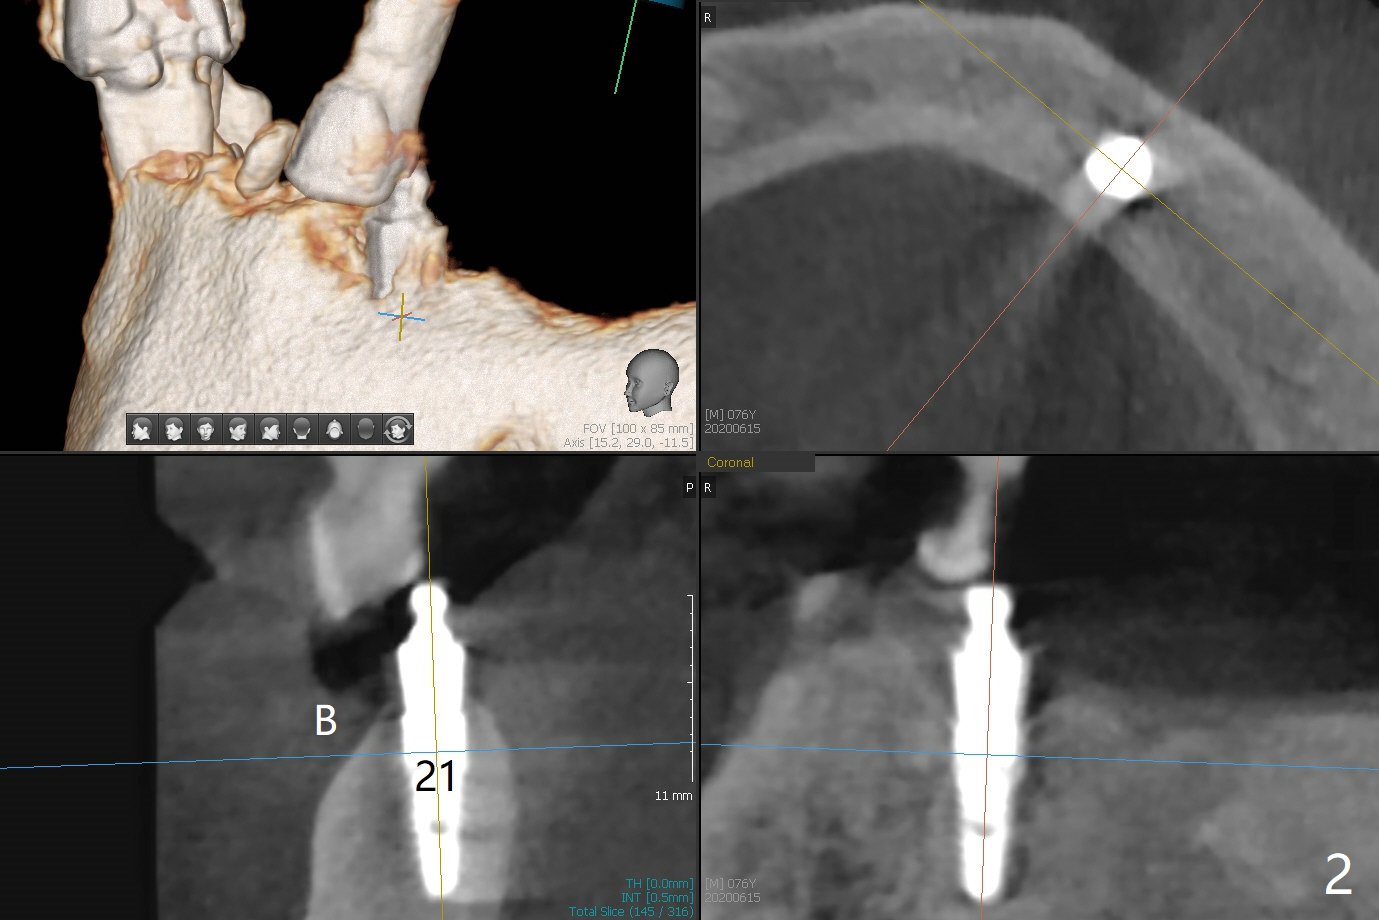

A 76-year-old man returns to clinic with chief complaint of loose top partial 2 years 3 months post #21 implant placement (Fig.1,2). The tooth #11 has mobility, while the socket of #13 heals and the tooth #1 is stable and functional (Fig.1). Two implants will be placed at #11 and 13 (Fig.3,4) with ball abutments (4 and 2 mm cuffs, respectively). Since the bone density is low at #13, bone expanders will be used as well as for sinus lift (implant 4x10 mm instead, PRF). Keep the tooth #11 as a denture one. Soft reline will be used to hold the abutments.